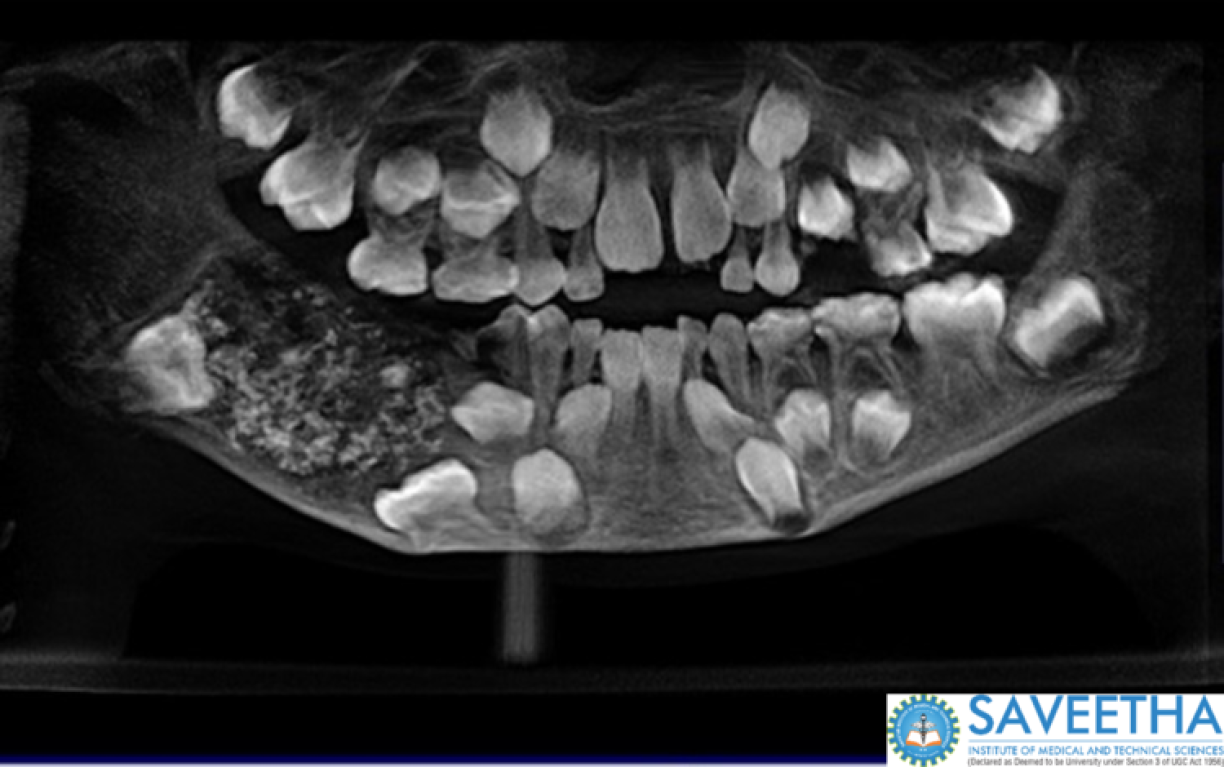

Les médecins ont pu identifier la masse, d’environ 200 grammes, et lui ont retiré après cinq heures d’opération permettant de préserver sa mâchoire. L’excroissance contenait 526 dents, toutes formées d’une structure avec une racine, de l’émail et une couronne. La plus petite mesurait environ 0,1 millimètre quand la plus grande mesurait 1,5 centimètre.